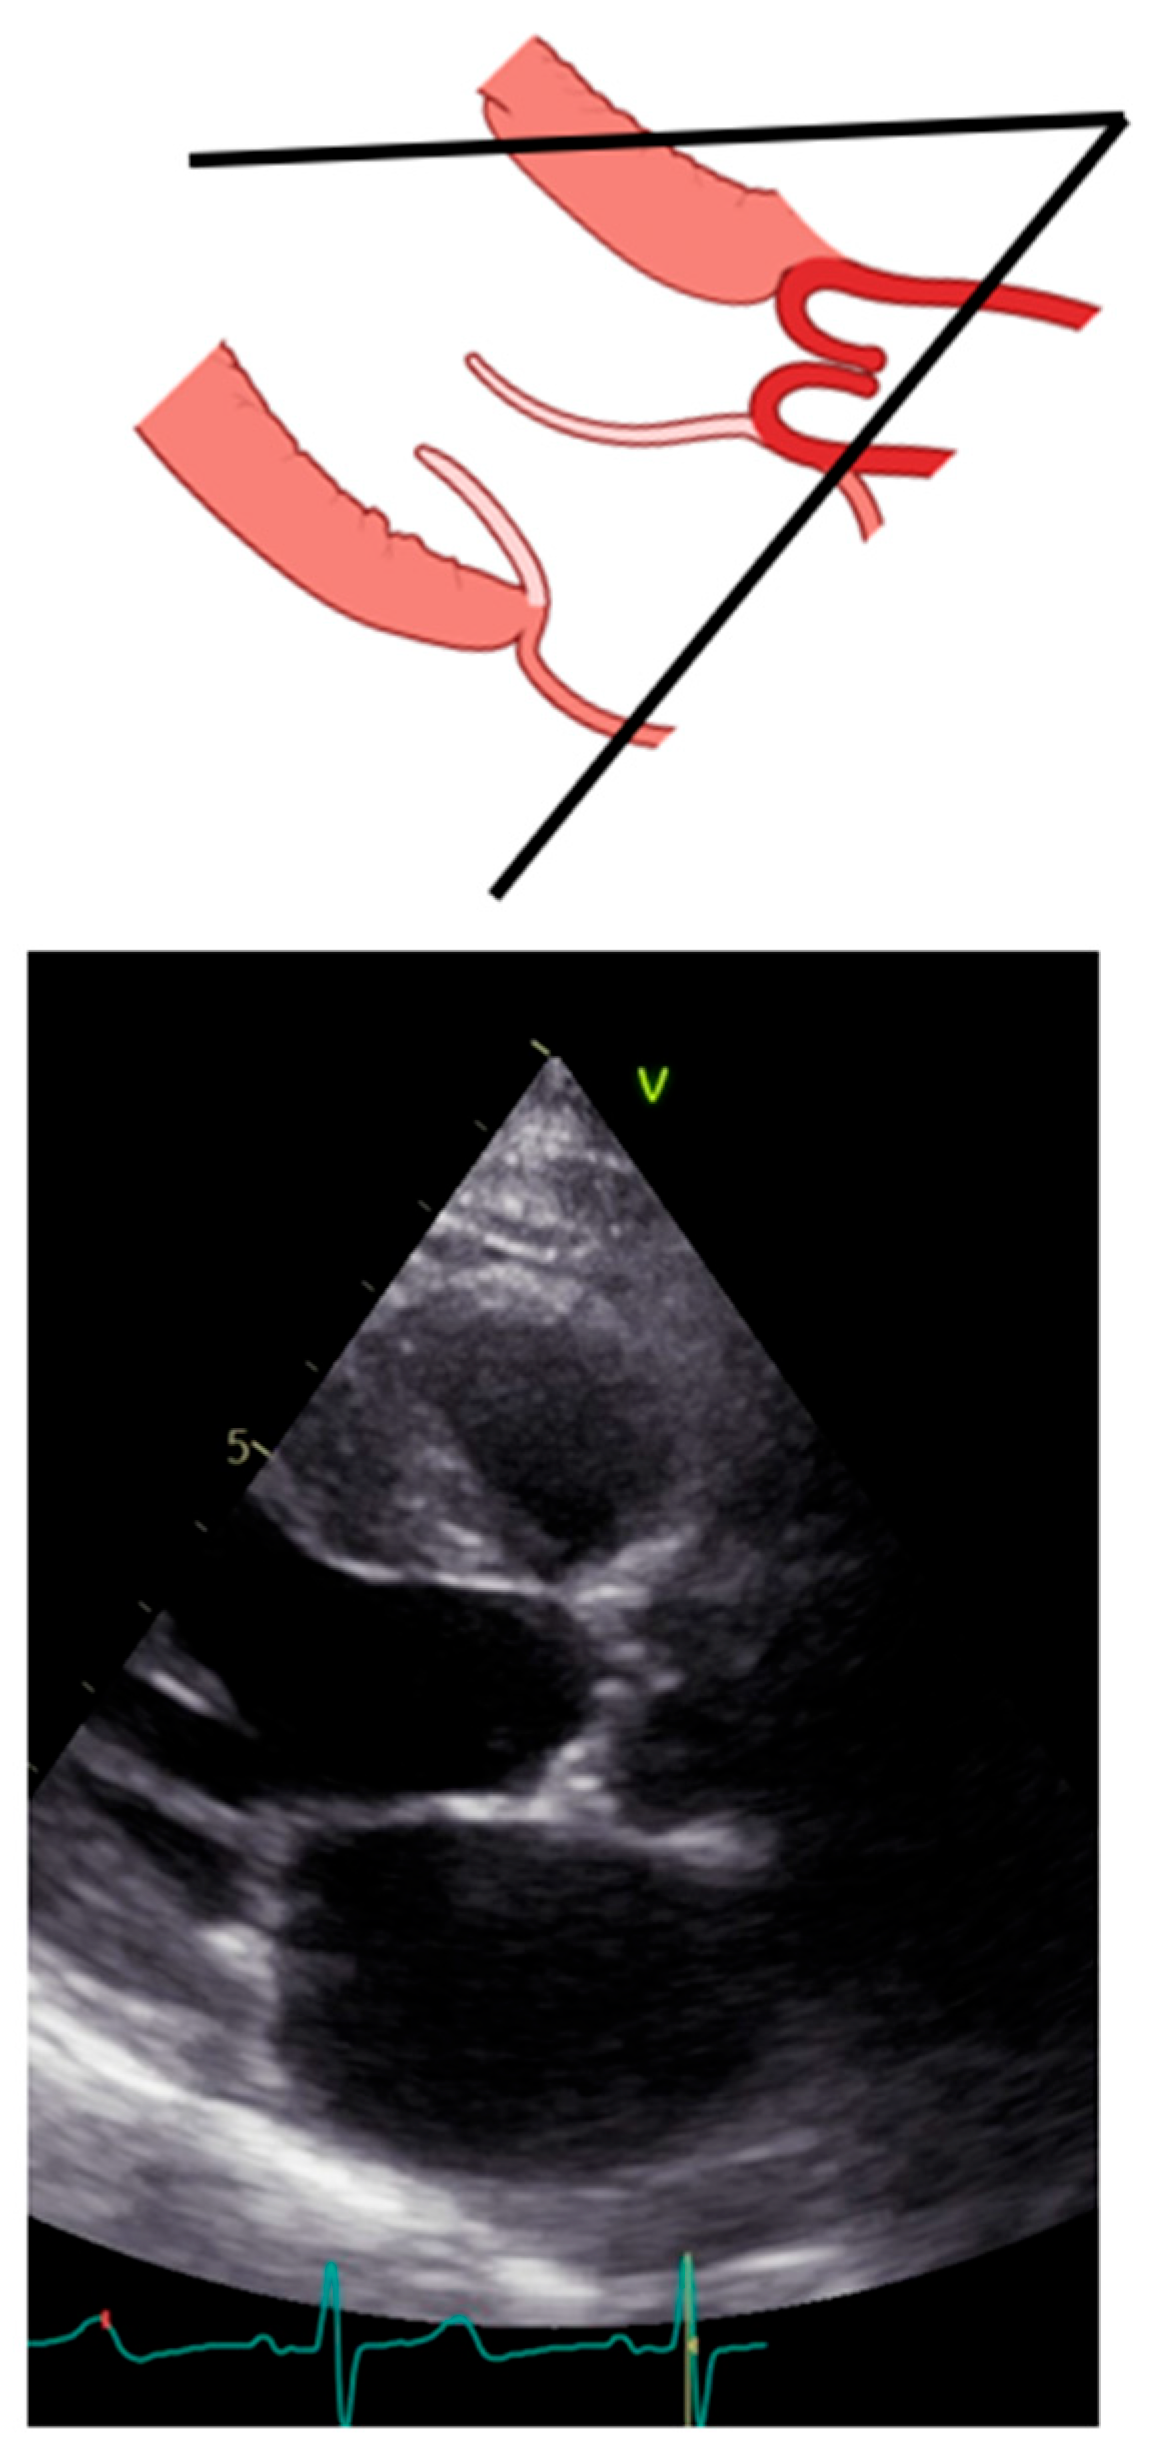

2. Long Axis View